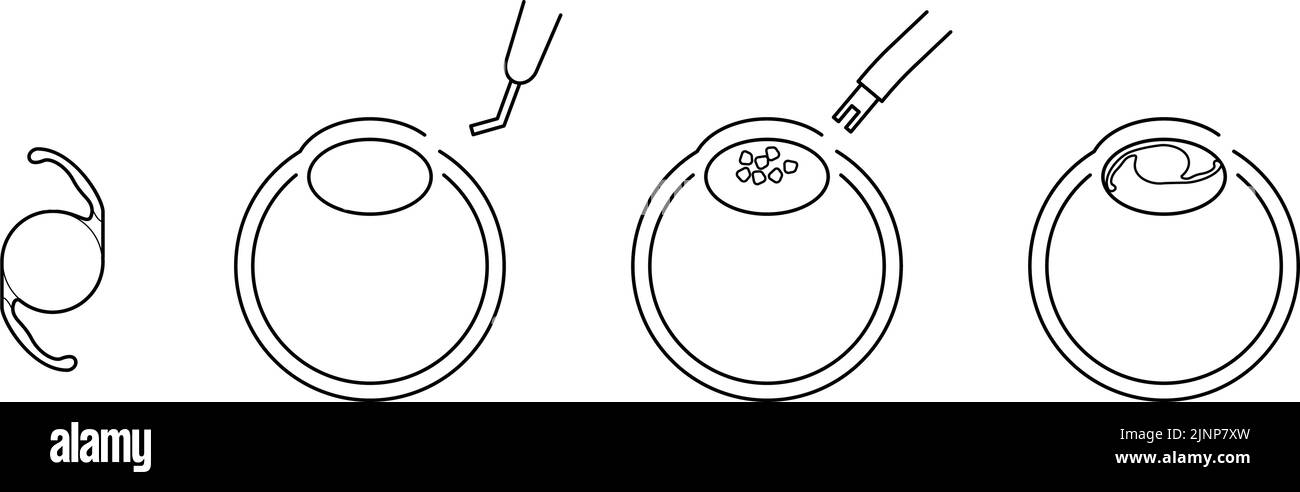

Flow of cataract surgery, illustrated illustration (line drawing) Stock Vectorhttps://www.alamy.com/image-license-details/?v=1https://www.alamy.com/flow-of-cataract-surgery-illustrated-illustration-line-drawing-image478076897.html

Flow of cataract surgery, illustrated illustration (line drawing) Stock Vectorhttps://www.alamy.com/image-license-details/?v=1https://www.alamy.com/flow-of-cataract-surgery-illustrated-illustration-line-drawing-image478076897.htmlRF2JNP7XW–Flow of cataract surgery, illustrated illustration (line drawing)